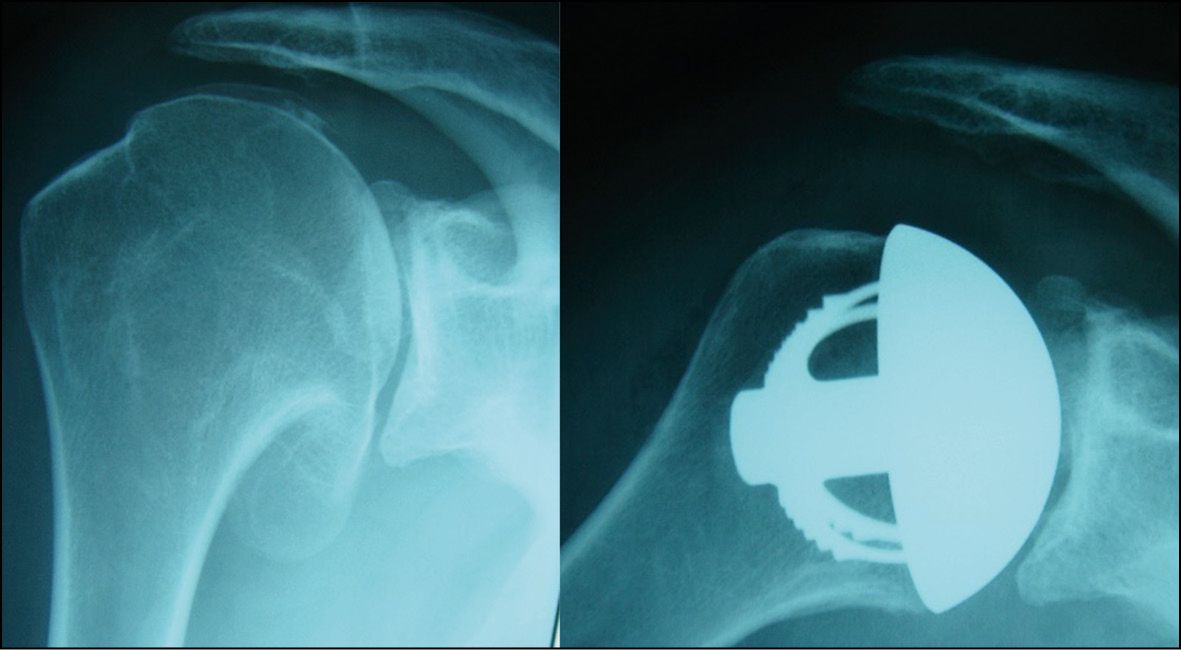

Globally, sales figures are easily dominated by anatomical designs, with Lima selling 44% stemless TSAa (anatomical) vs. 9% stemless TSAr (reverse). Looking just at France, the birthplace of stemless, these figures from Lima are different yet again: 84% stemless TSAa vs. 43% stemless TSAr. Osteonecrosis of the humeral head is a good indication for a stemless implant because resurfacing the humeral head is a simple and minimally-invasive procedure. Likewise, a resurfacing hemiarthroplasty may be indicated for primary concentric osteoarthritis of the shoulder in patients under 50 if the glenoid is in good condition (Fig. 10).

Concentric osteoarthritis in a young subject is the perfect indication for stemless TSAa because there will be good-quality bone stock and a future revision will be made easier by the use of a stemless design. Longer survival can also be achieved by using a hybrid glenoid component to avoid the need for cement (Fig. 12).